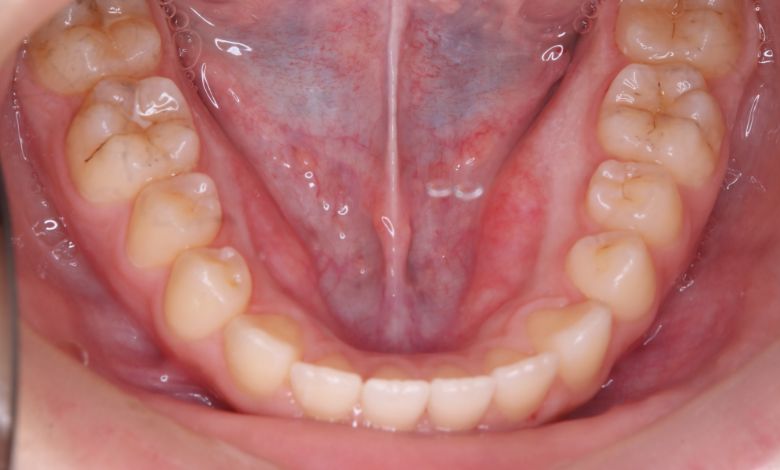

歯列弓はV字型に狭く、左右の犬歯が唇側に大きく転位している状態

前歯部では3歯が大きく重なり、ねじれや傾斜も伴っている。歯列弓は狭く、U字型から逸脱した非対称な形態

歯列全体に強いガタつき(叢生)が見られ、特に上下の前歯は重なりが大きく、見た目にも咬み合わせにも

大きな不調和がありました。歯列弓はV字型に狭く、他院では抜歯を伴う矯正治療が提案されていました。

当院では抜歯を行わず、歯列弓を広げてスペースを確保する治療を選択。歯並びは自然なU字型へと整い、前歯の重なりも解消されました。咬み合わせが改善され、見た目の美しさはもちろん、咀嚼機能や清掃性の向上といった機能面でも良好な結果が得られています。